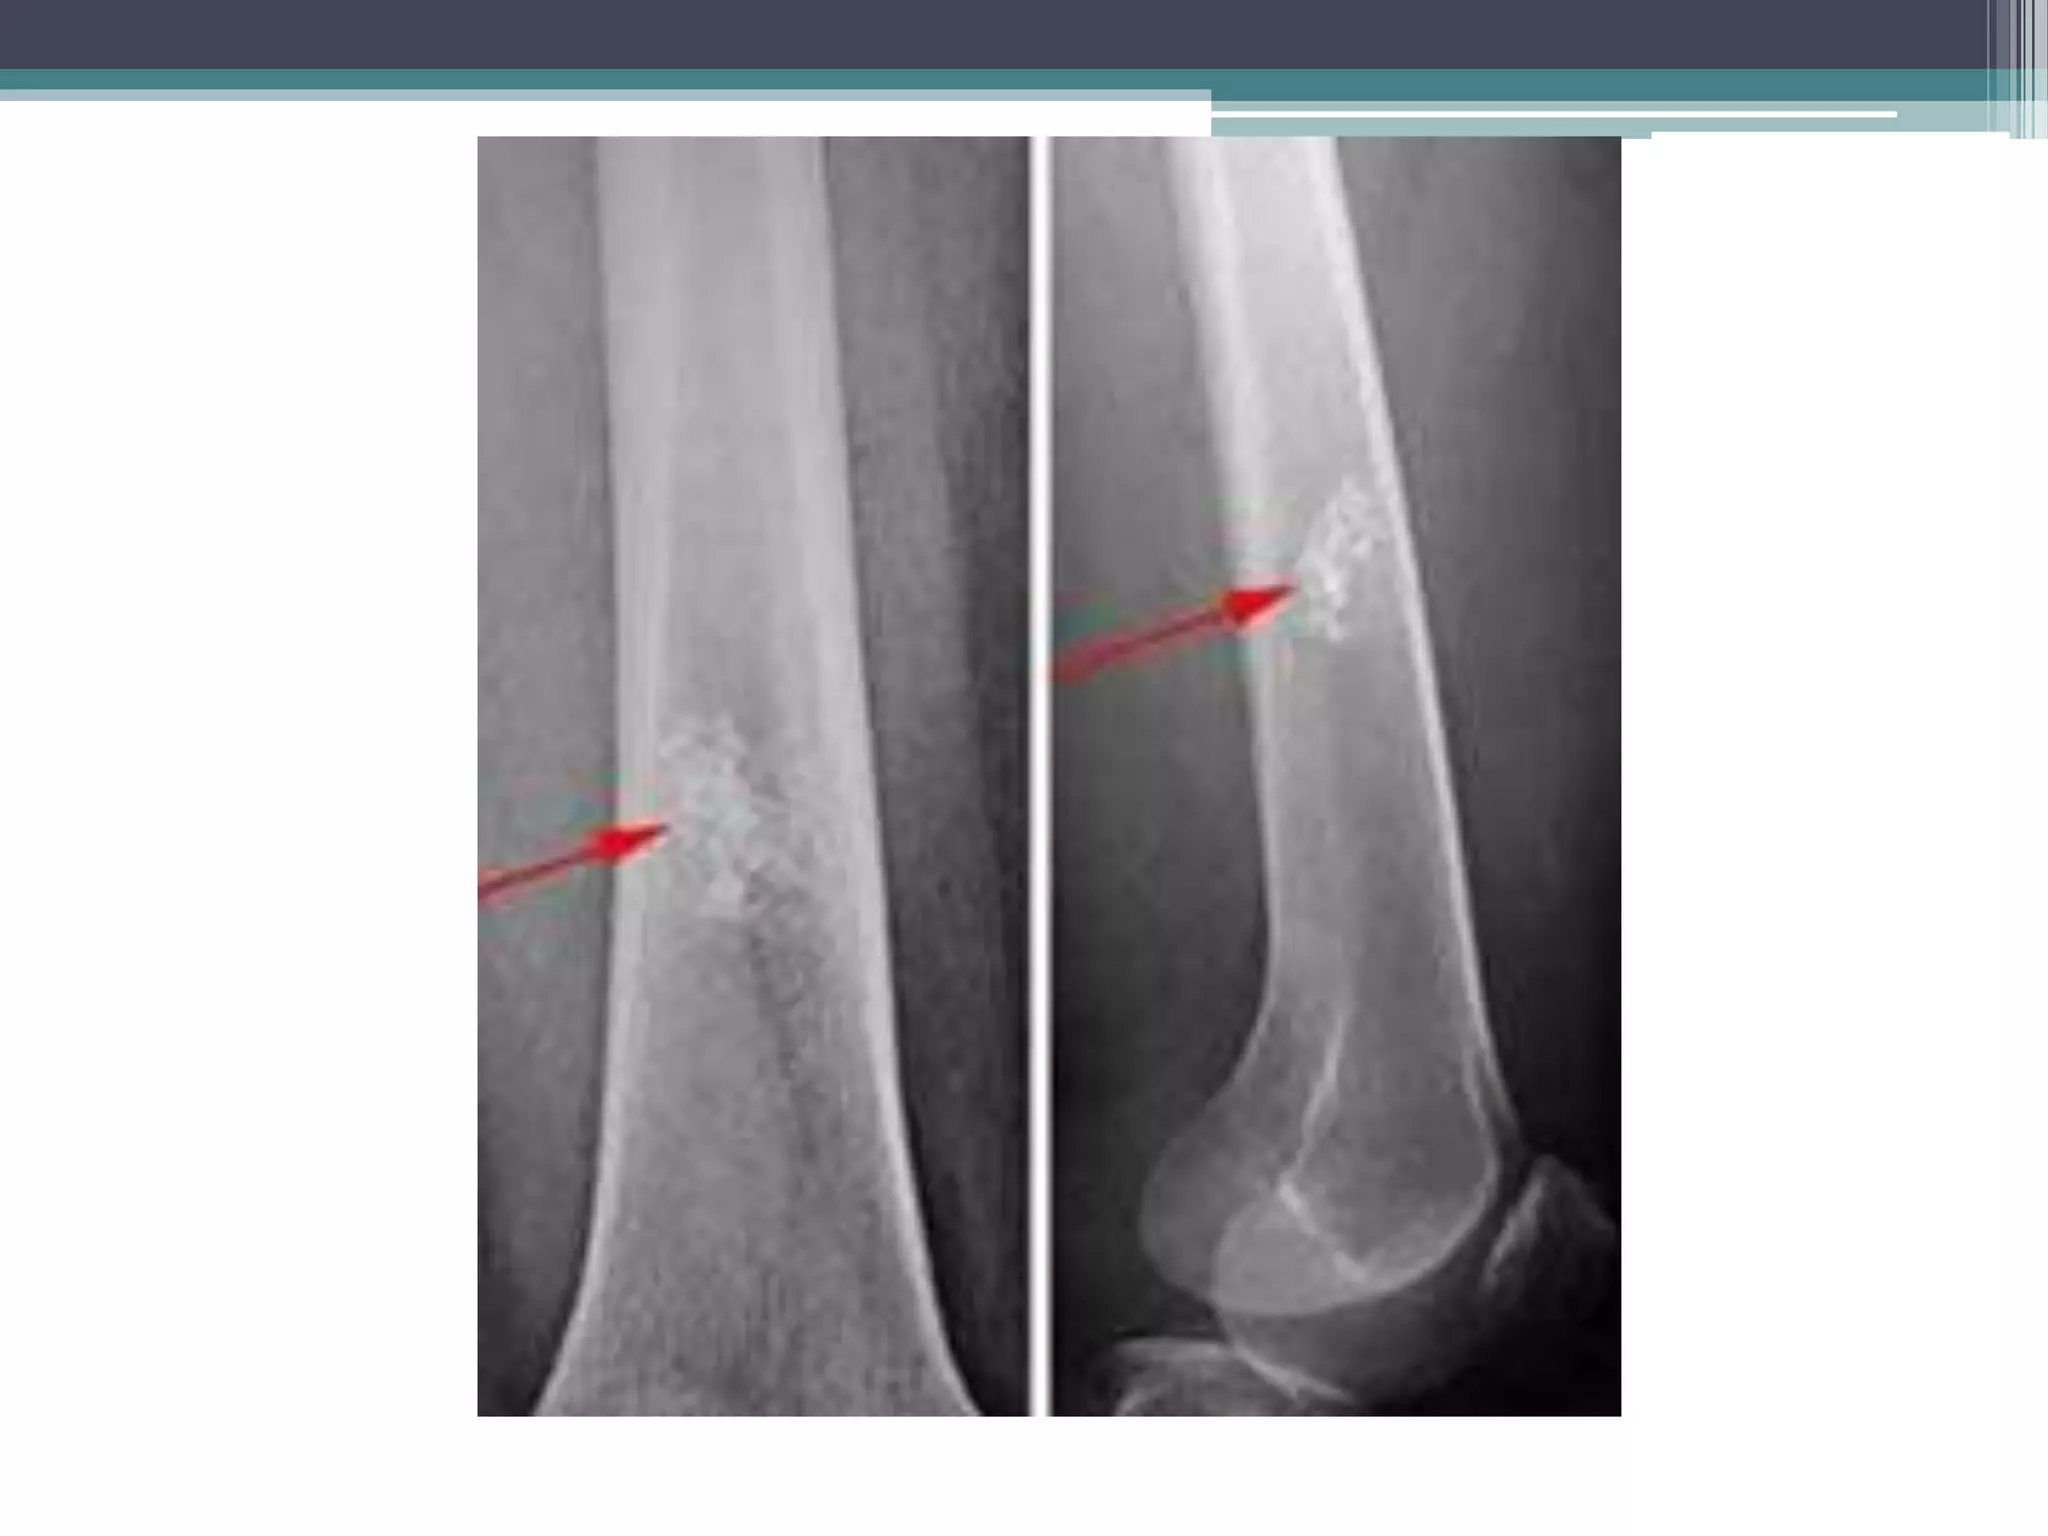

Chondrosarcoma

• Plain films show

• large osteolytic lesions.

• Central flecks of calcification

Chondrosarcoma • Plain filmsshow • large osteolytic lesions. • Central flecks of calcification